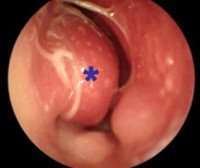

J34.3 Гипертрофия носовой раковины